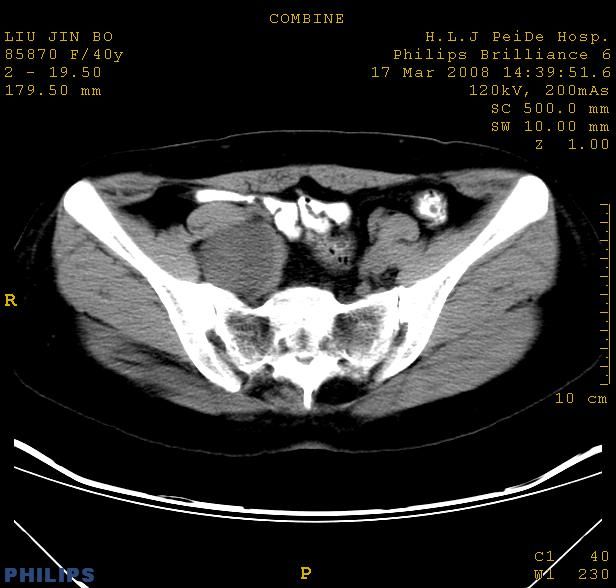

以下是引用qiuleiyu在2008-4-27 12:36:00的发言:[br]支持;右侧腰大肌后方神经源性肿瘤可能大,神经节细胞瘤?

以下是引用形影不离在2008-4-27 14:11:00的发言:[br]1.考虑右侧腰大肌脓肿。[br]2.左侧附件区炎症。[br]3.子宫增大,建议:进一步检查。